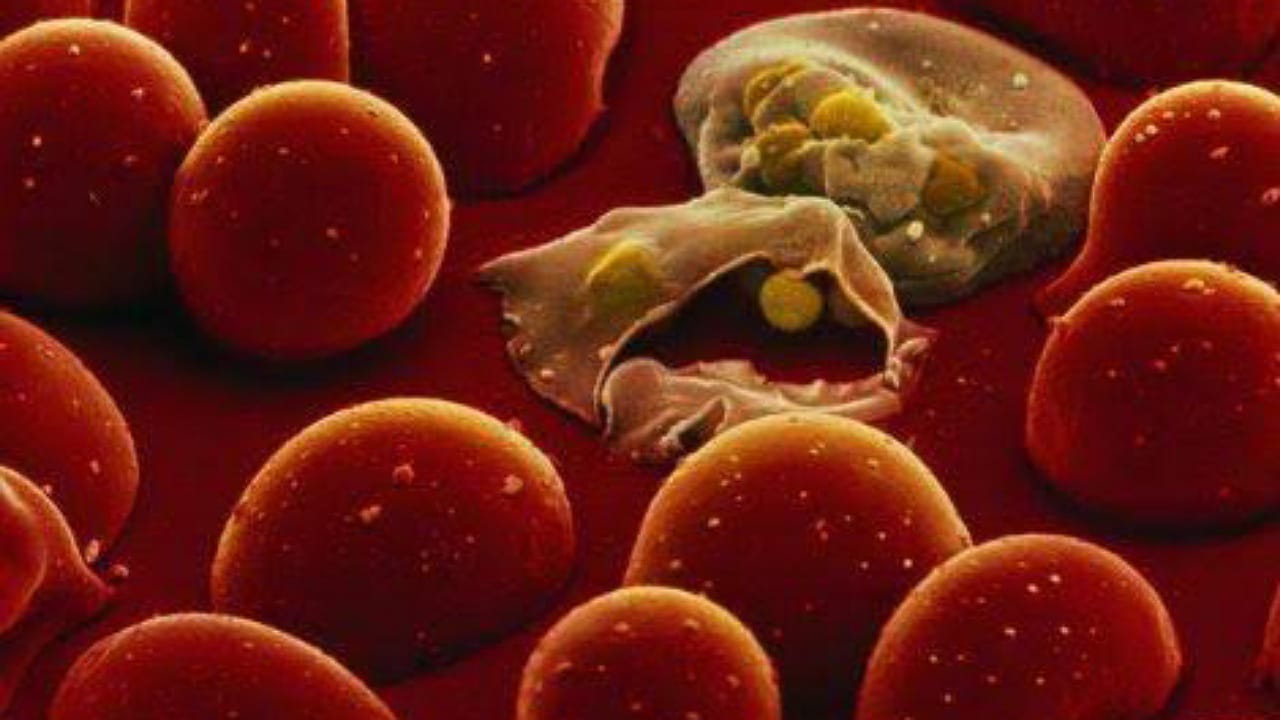

أسباب وأعراض أنيميا الفول